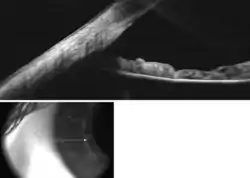

Gonioscopy of the anterior chamber angle. Labeled structures: 1. Schwalbe's line, 2. Trabecular meshwork (TM), 3. Scleral spur, 4. Ciliary body, 5. Iris

Gonioscopy of the anterior chamber angle

Anterior chamber angle cross-section imaged by an SD-OCT.